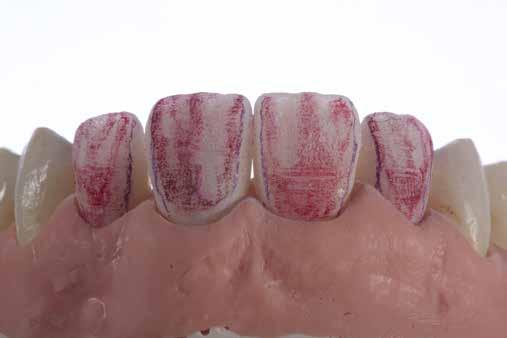

Az előzetes állapotfelmérést és a kezelés megtervezését követően a fogakat minimál invazív módon preparáltuk (1. a-b ábrák), majd az előkészített fogak ínybarázdáiba fonalbehelyező eszköz segítségével (113 Serrated Gingival Cord Packer, Hu-Friedy, Chicago, Illinois) teflonszalagot helyeztünk (Loctite Thread Seal Tape, Henkel Loctite Corp., Egyesült Államok), (1. c ábra). A hagyományos retrakciós fonalak helyett, a rugalmasságuk miatt előnyösebbnek tartjuk a teflonszalagok használatát. A kofferdámot (Dental Dam, Nic Tone, Bukarest, Románia) az előkészített fogakon kívül, az azoktól disztálisan elhelyezkedő egy-egy fognak megfelelően is perforáltuk.

Mivel a felső fogív első kisőrlőfogtól ellenoldali első kisőrlőfogig terjedő részét terveztük kerámia héjak segítségével ellátni (14-24), ezért az izolálást ugyanezen fogív második kisőrlőfogtól második kisőrlőfogig terjedő részére (15-25) helyeztük fel (2. a ábra). A kofferdám rögzítését a második kisőrlőfogakra helyezett kapcsok segítségével (Rubber Dam Clamps #2, Hu-Friedy, Chicago, Illinois, Egyesült Államok) biztosítottuk (2. b ábra). Ezt követően a gumilepedő fogakat körülvevő szélét kézi fonalbehelyező eszközzel és finom levegőáramlattal az ínybarázdákba forgattuk. A folyamat a következőképpen zajlott: a kézi eszközzel a kofferdámot a fognyaknak megfelelően finoman a szulkusz irányába fordítjuk, majd az eszköz végét a fognyaknak megfelelően vezetjük, miközben a lepedőt a puszterből jövő levegő segítsé-

A gumilepedő és a kiválasztott kapcsok (A). A kisőrlőfogakra helyezett kapcsok stabilizálják a kofferdámot (B). A gumilepedő ínybarázdákba történő beforgatása fonalbehelyező eszköz és levegőáramlat segítségével (C). Közvetlenül a héjak felhelyezése előtt a frontfogakra helyezett kapcsok (D).

ábra: A kapcsok eltávolítása és a kismetszőfogakra készült héjak beragasztása. A kapcsok nagymetszőfogakról történő eltávolítása (A). A kapcsok eltávolítása után látható állapot (B). A nagymetszőfogak és a szemfogak teflonszalaggal történő izolálása (C). A kismetszőfogak ínykapcsokkal történő kiegészítő izolálása (D). A héjak átadása után látható állapot (E).

gével finoman az ínybarázdába fordítjuk (2. c ábra). Azokra a fogakra, amelyekre aktuálisan héjakat akartunk helyezni, ezen felül kiegészítő kapcsokat is helyeztünk (Hygenic Brinker Clamp #B4, Coltene/Whaledent Inc., Cuyahoga Falls, Ohio, Egyesült Államok), (2. d ábra) Ebben a stádiumban érdemes a héjakat még bármilyen ragasztóanyag vagy próbapaszta nélkül a helyükre illeszteni (dry tryin). Erre azért volt szükség, hogy még a tényleges ragasztási folyamat megkezdése előtt ellenőrizni tudjuk a restaurátum és a fog pontos illeszkedését, valamint a széli záródási vonalhoz való akadálytalan hozzáférést (3. a ábra). Ideális esetben a héjak felhelyezését párosával, a középvonaltól disztál felé haladva végezzük. Ennek megfelelően a jobb (1.1) és bal felső nagymetszőfogakra (2.1) kapcsokat helyeztünk, majd a szomszédos fogakat teflonszalag segítségével izoláltuk. Ezt követően az 1.1-es és 2.1-es fogak héjak elhorgonyzására szolgáló felszíneit 32%os foszforsavval (Uni-Etch w/BAC, Bisco Dental, Schaumburg, Illinois, Egyesült Államok) 30 másodpercen keresztül kondicionáltuk. Ez után a felszínek vízzel történő lemosása és óvatosan